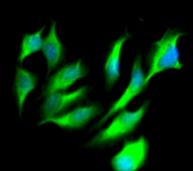

IF:

Immunofluorescent analysis of Hela cells using CSB-MA0157131A0m at a dilution of 1:100 and Alexa Fluor 488-congugated AffiniPure Goat Anti-Mouse IgG(H+L)

Immunofluorescent analysis of PC-3 cells using CSB-MA0157131A0m at a dilution of 1:100 and Alexa Fluor 488-congugated AffiniPure Goat Anti-Mouse IgG(H+L)

Immunofluorescent analysis of U251 cells using CSB-MA0157131A0m at a dilution of 1:100 and Alexa Fluor 488-congugated AffiniPure Goat Anti-Mouse IgG(H+L)